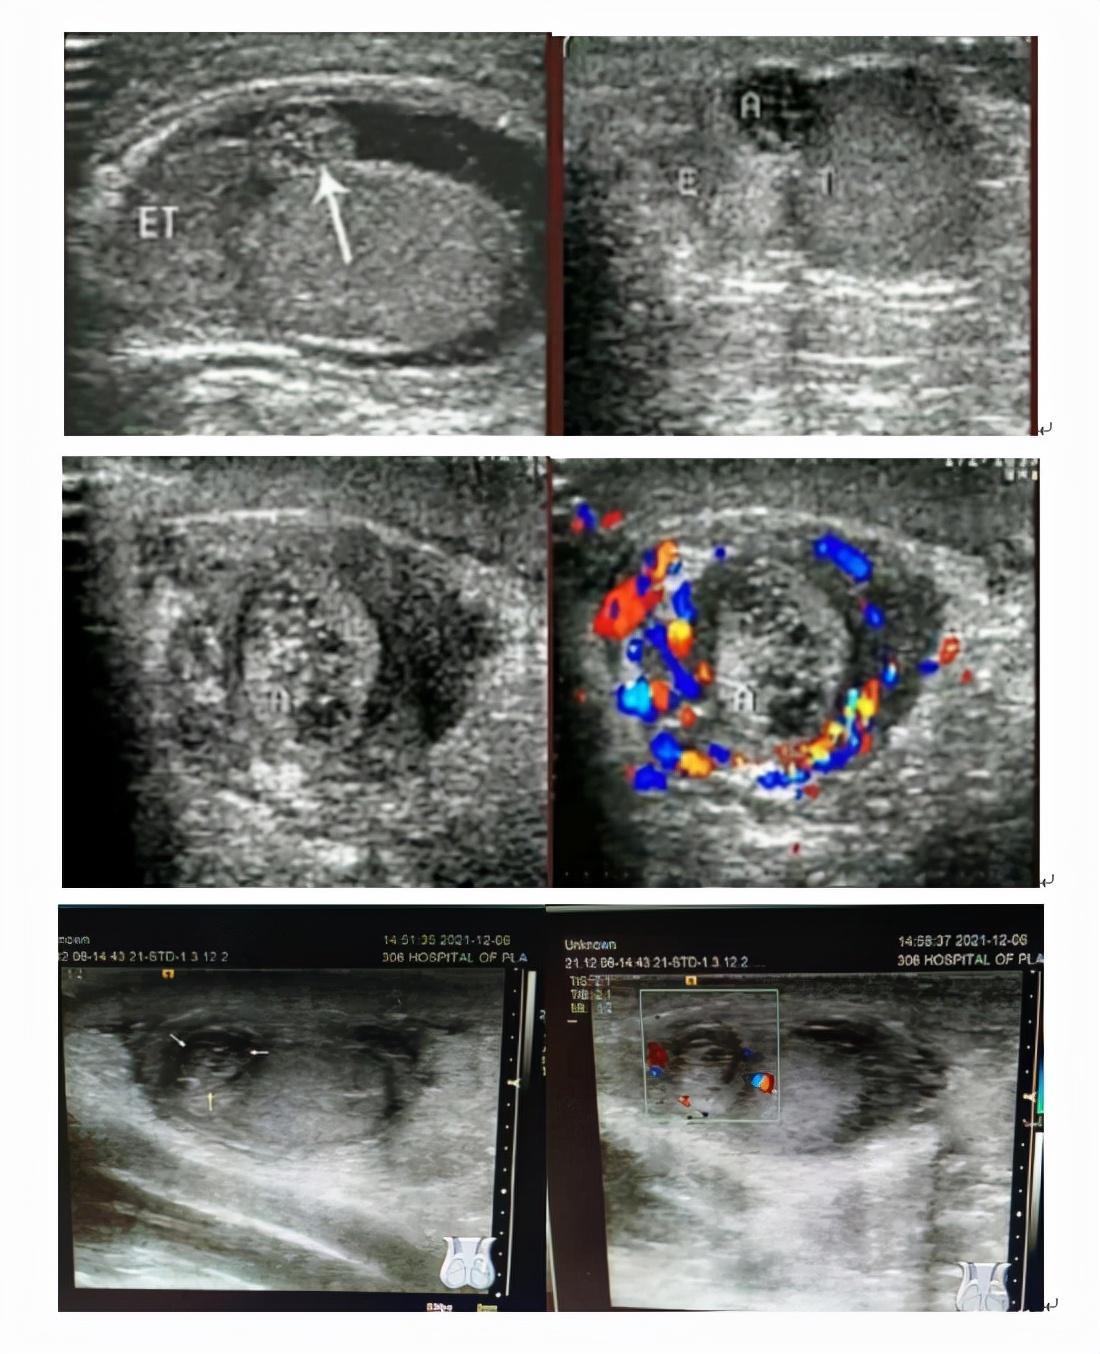

睾丸附件扭转的超声图像及表现

超声表现主要为:①患侧阴囊壁水肿,附件肿大,回声欠均或不均;②扭转的附件位于附睾头旁、睾丸上极或附睾头与睾丸上极之间,以后者多见;③附件附着处轻度肿大,回声增强,附着处组织血供增多,而附件内无血流信号;④扭转后可发生囊性变、钙化、脱落。

超声因其无创、快捷、准确、可重复性强等优点,成为诊断该病的最佳检查方法,诊断睾丸附件扭转超声须探及直接征象,结合病史、症状、体征,诊断率可大大提高。